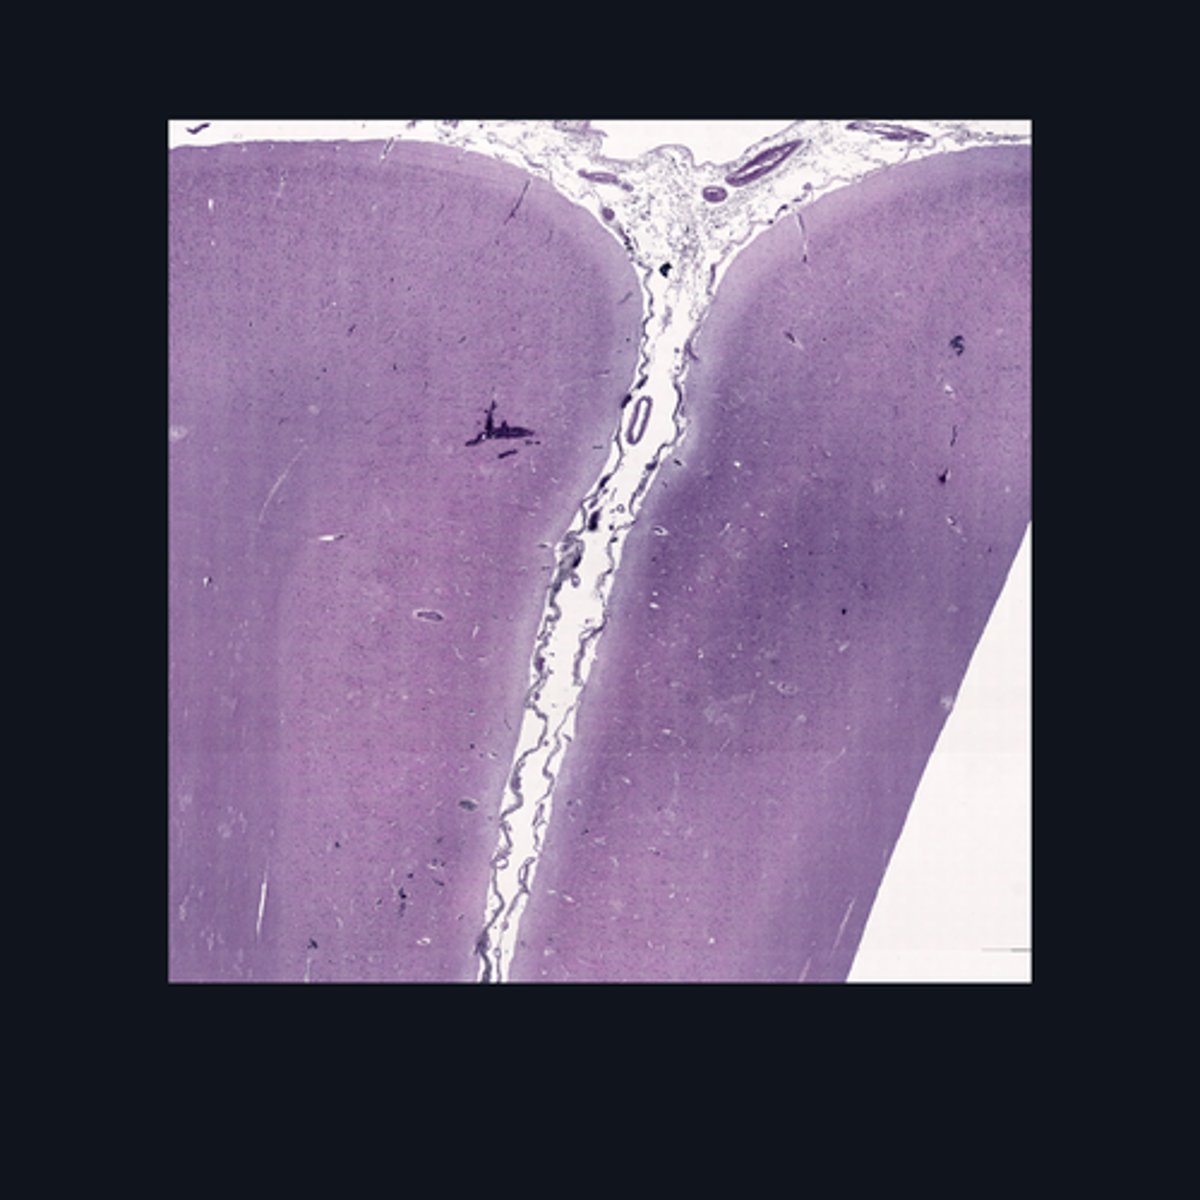

Identify the region of the spinal cord in the given image.

(top to bottom)

Ventral median fissure

White matter

Ventral horns

Central Canal

Central commissure

Dorsal midline sulcus

Dorsal horns

Identify the parts of the sacral region of the spinal cord.

FALSE

T or F: The white matter in this region of the spinal cord is larger than the white matter in the thoracic region of the spinal cord.

Upper Cervical region

Identify the region of the spinal cord in the given image.

(top to bottom)

White matter

Ventral horn of gray matter

Central canal

Central Commissure

Dorsal horn of the gray matter

Dorsal Midline Sulcus

Identify the structures found in the upper cervical region of the spinal cord.